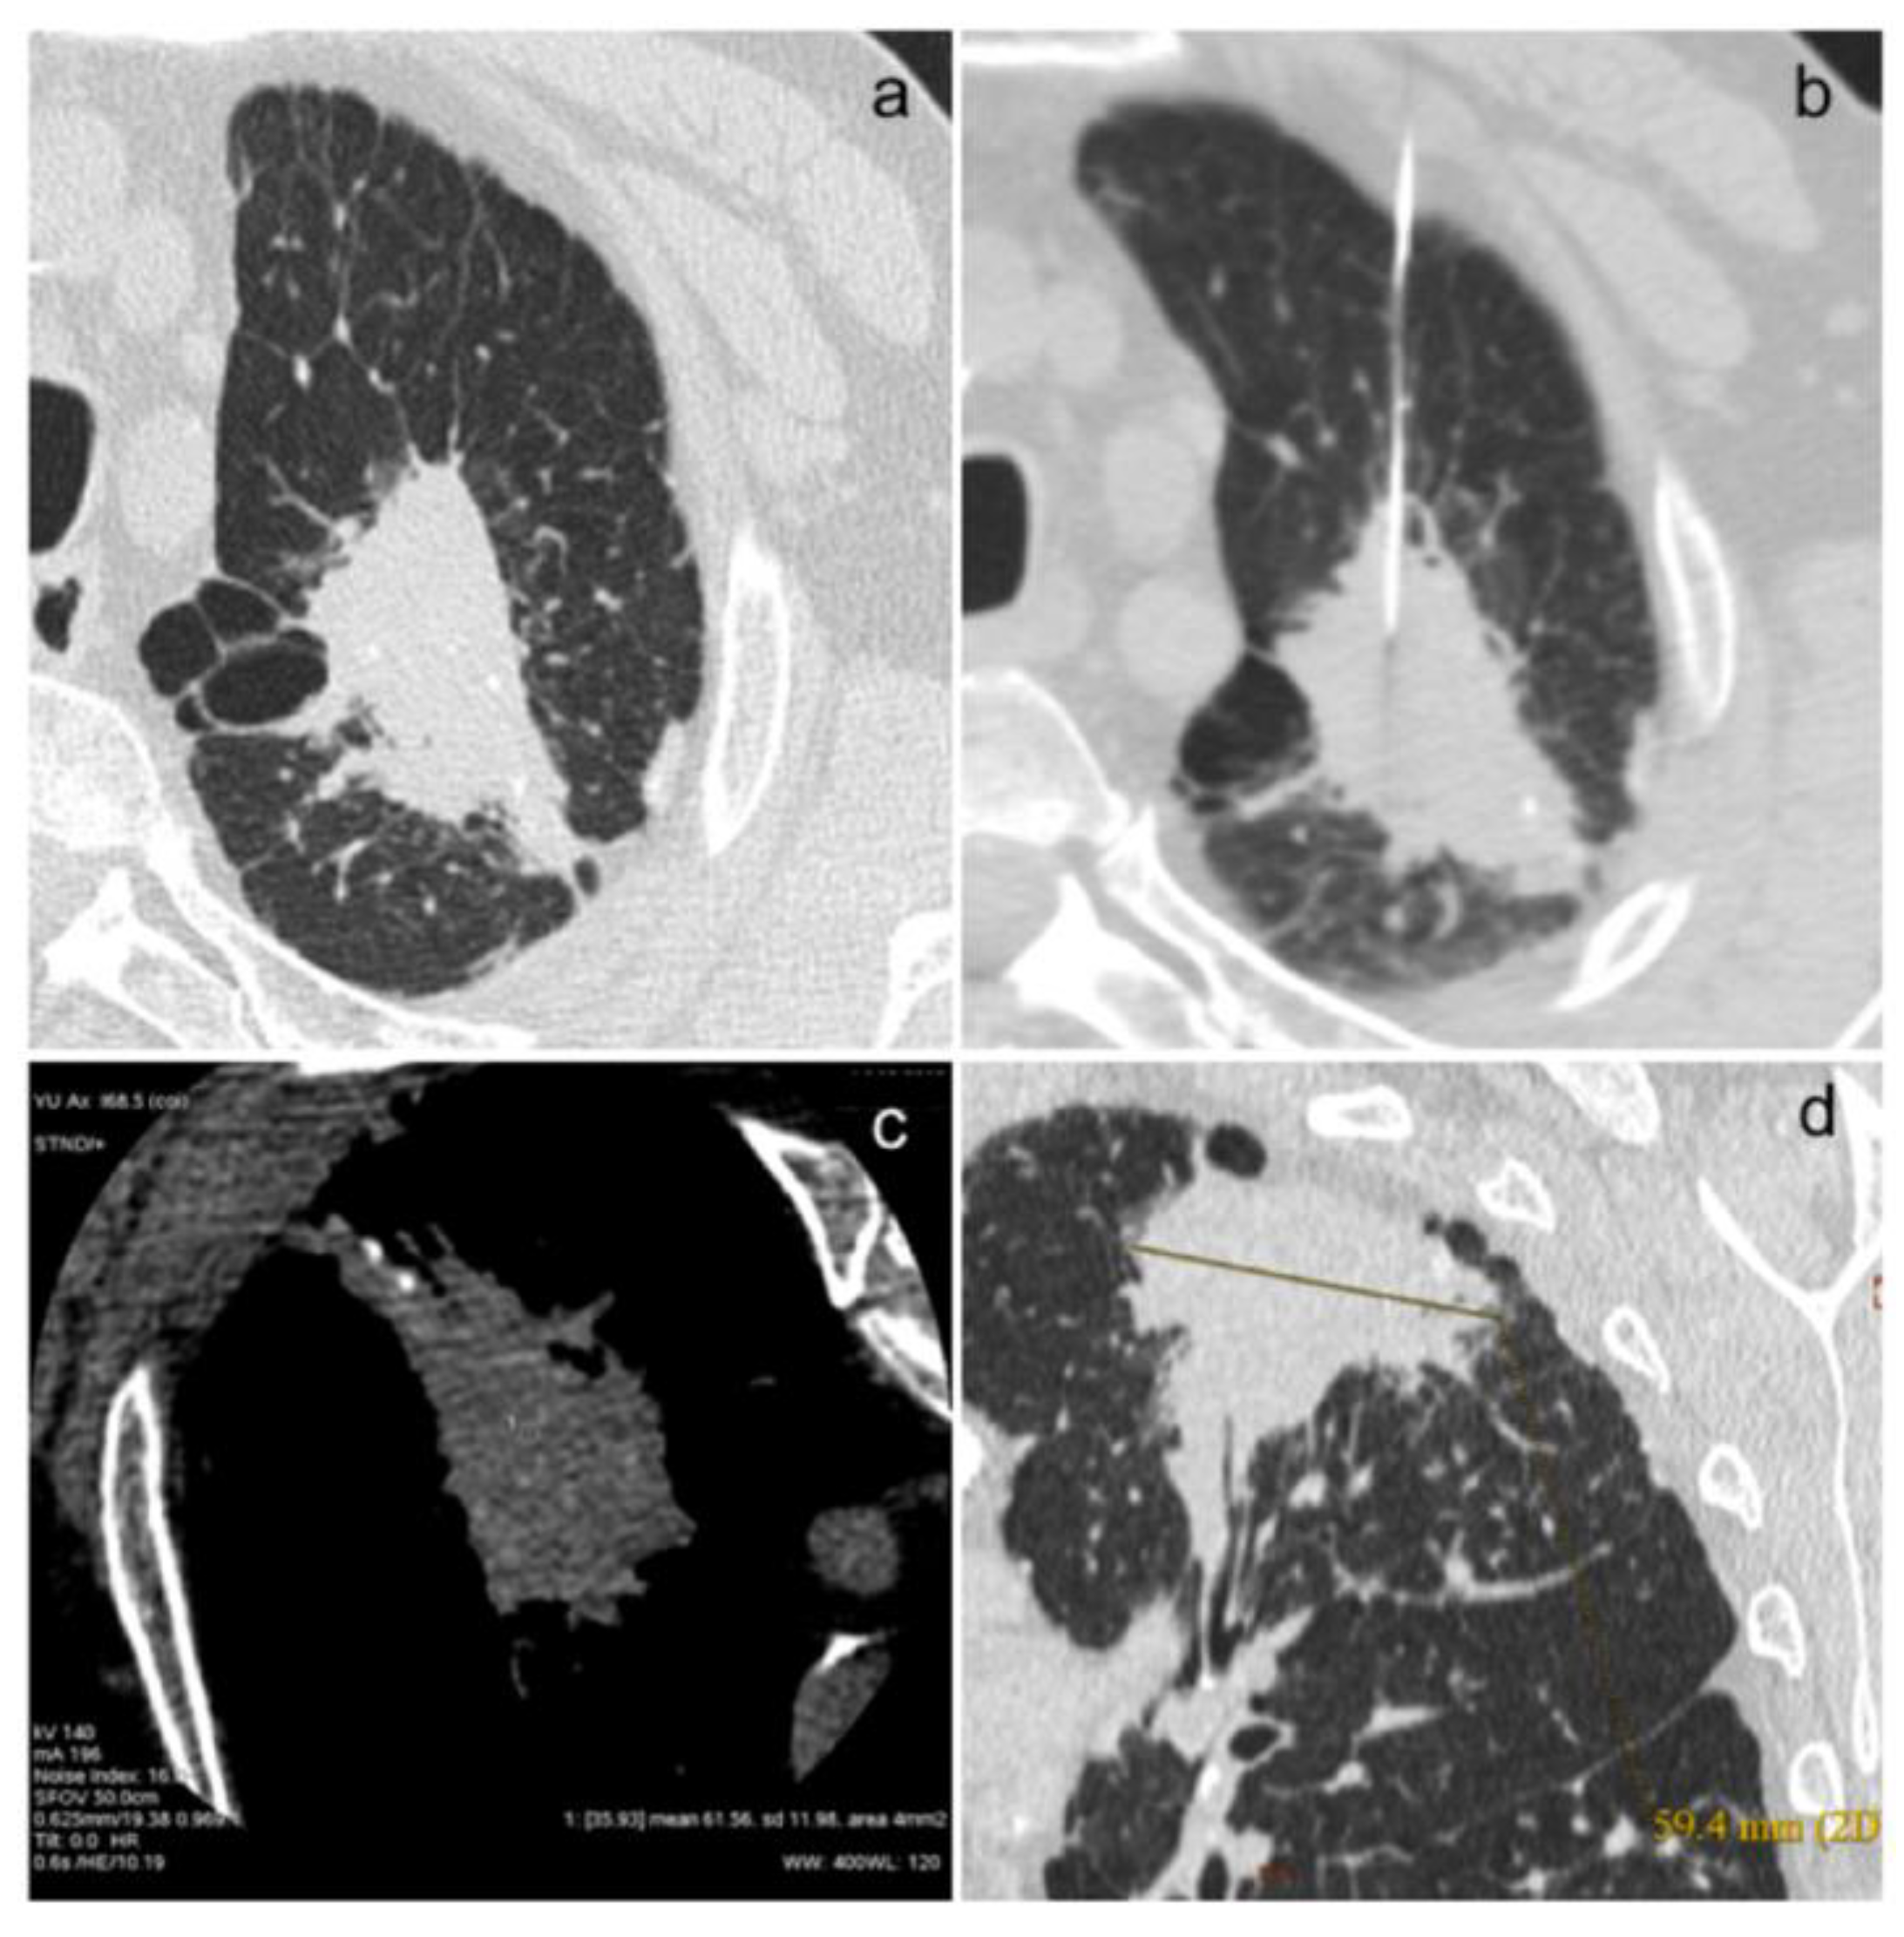

In Figure 1a–d and Figure 2a–e, we show some images from our patients.

Figure 1. (ad). This is the case of an 80-year-old patient with acinar (40%) and solid (20%) adenocarcinoma with in situ areas of lepidic morphology (40%) and adenocarcinomatous infiltration of the visceral pleura (a), confirmed on biopsy examination (b). The neoplastic lesion has a high density (61.56 HU, (c)) and a size of about 60 mm (d).